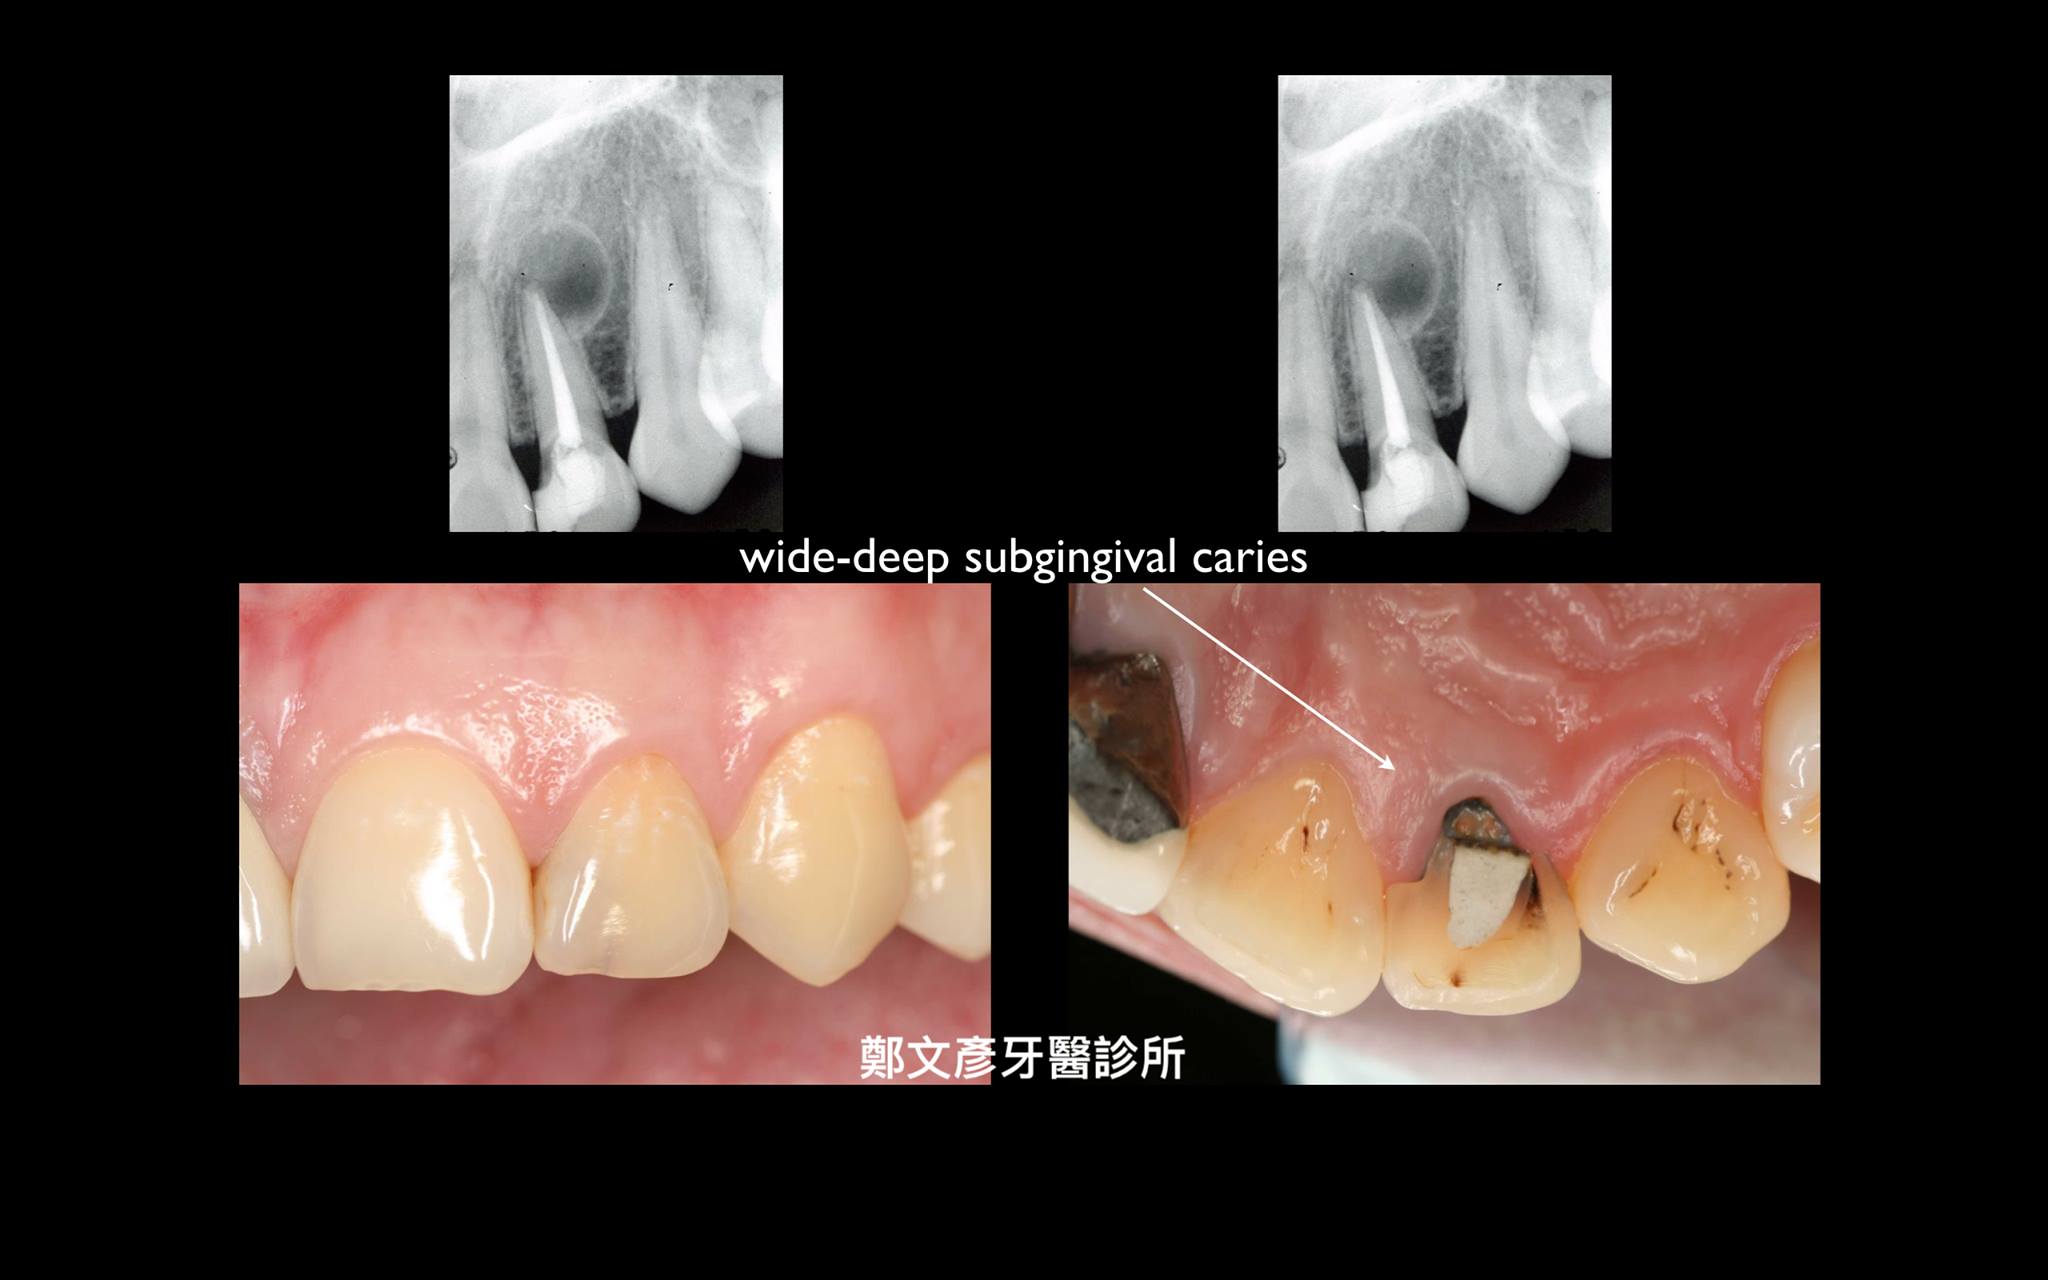

前牙植牙美學及軟組織轉移

Role of granulation tissue in socket preservation